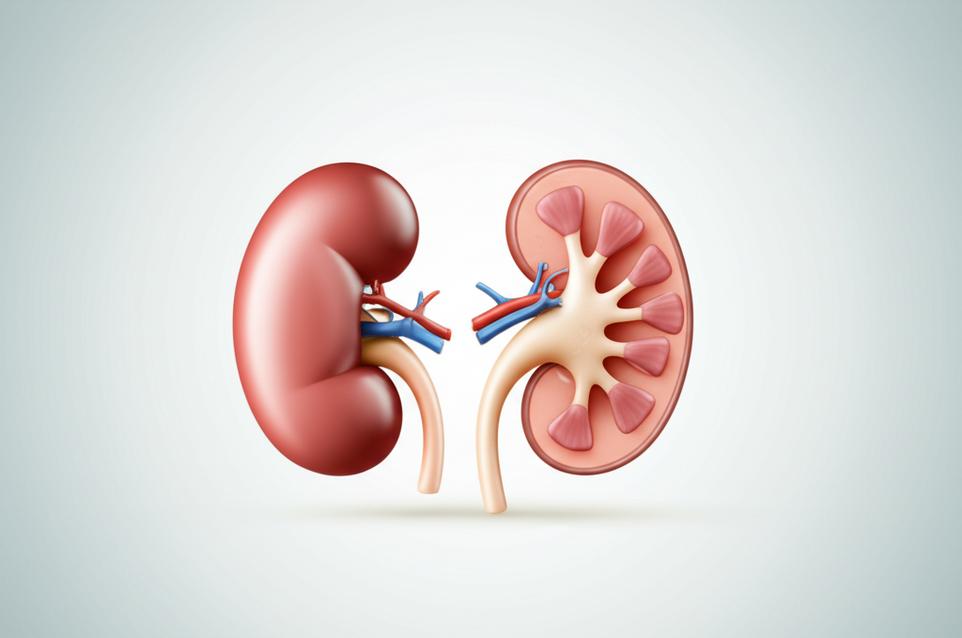

ความเข้าใจพื้นฐานเรื่องไต: อวัยวะสำคัญกับการเสื่อมตามวัย

“ไต” สองข้างทำหน้าที่เปรียบเสมือนโรงบำบัดน้ำเสียและศูนย์ควบคุมสมดุลอันซับซ้อนของร่างกาย ทุกวันไตจะกรองเลือดปริมาณมหาศาล เพื่อกำจัดของเสียส่วนเกิน สารพิษ และรักษาสมดุลของน้ำ เกลือแร่สำคัญ เช่น โซเดียม โพแทสเซียม แคลเซียม ฟอสฟอรัส รวมถึงรักษาสมดุลกรด-ด่างของเลือด นอกจากนี้ ไตยังสร้างฮอร์โมนสำคัญที่เกี่ยวข้องกับการสร้างเม็ดเลือดแดง (Erythropoietin) การควบคุมความดันโลหิต (Renin) และการรักษาสุขภาพกระดูก (Active Vitamin D) การทำงานที่หลากหลายและหนักหน่วงนี้ ทำให้ไตเป็นอวัยวะที่อ่อนแอต่อการเสื่อมสภาพเมื่อเวลาผ่านไป หรือเมื่อต้องเผชิญกับปัจจัยกระตุ้นต่างๆ

เมื่ออายุเพิ่มขึ้น ประสิทธิภาพการกรองของไตย่อมลดลงตามธรรมชาติ ซึ่งเป็นส่วนหนึ่งของกระบวนการชราภาพ แต่กระบวนการนี้สามารถเร่งให้เร็วขึ้นได้จากปัจจัยภายนอกและภายใน ไตของเรามีหน่วยกรองเล็กๆ นับล้านหน่วยที่เรียกว่า “เนฟรอน” (nephrons) เมื่อไตเริ่มเสื่อม จำนวนเนฟรอนเหล่านี้จะค่อยๆ ลดลงและเสียหาย ทำให้ความสามารถในการกรองเลือดและรักษาสมดุลของร่างกายลดลง การอักเสบเรื้อรังในระดับเซลล์ (chronic inflammation) ภาวะเครียดออกซิเดชั่น (oxidative stress) และการสะสมของสารพิษ เป็นปัจจัยสำคัญที่เร่งให้เกิดการเสื่อมของเนฟรอน ภาวะเหล่านี้มักเป็นผลมาจากพฤติกรรมการใช้ชีวิตและโภชนาการที่ไม่เหมาะสม การทำความเข้าใจกลไกเหล่านี้เป็นสิ่งสำคัญในการวางแผนดูแลสุขภาพไตเชิงป้องกัน เพื่อชะลอความเสื่อมและรักษาประสิทธิภาพการทำงานของไตให้นานที่สุด.